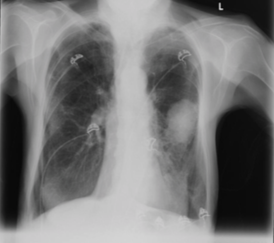

A 78yo male becomes septic following pneumonia. Over the next 24-48 hours, his SOB worsens and his oxygen saturation drops

ARDS

Other causes: aspiration, inhalation injury, acute pancreatitis, trauma, radiation, transfusion reaction, fat embolism, DIC, drug overdose, idiopathic